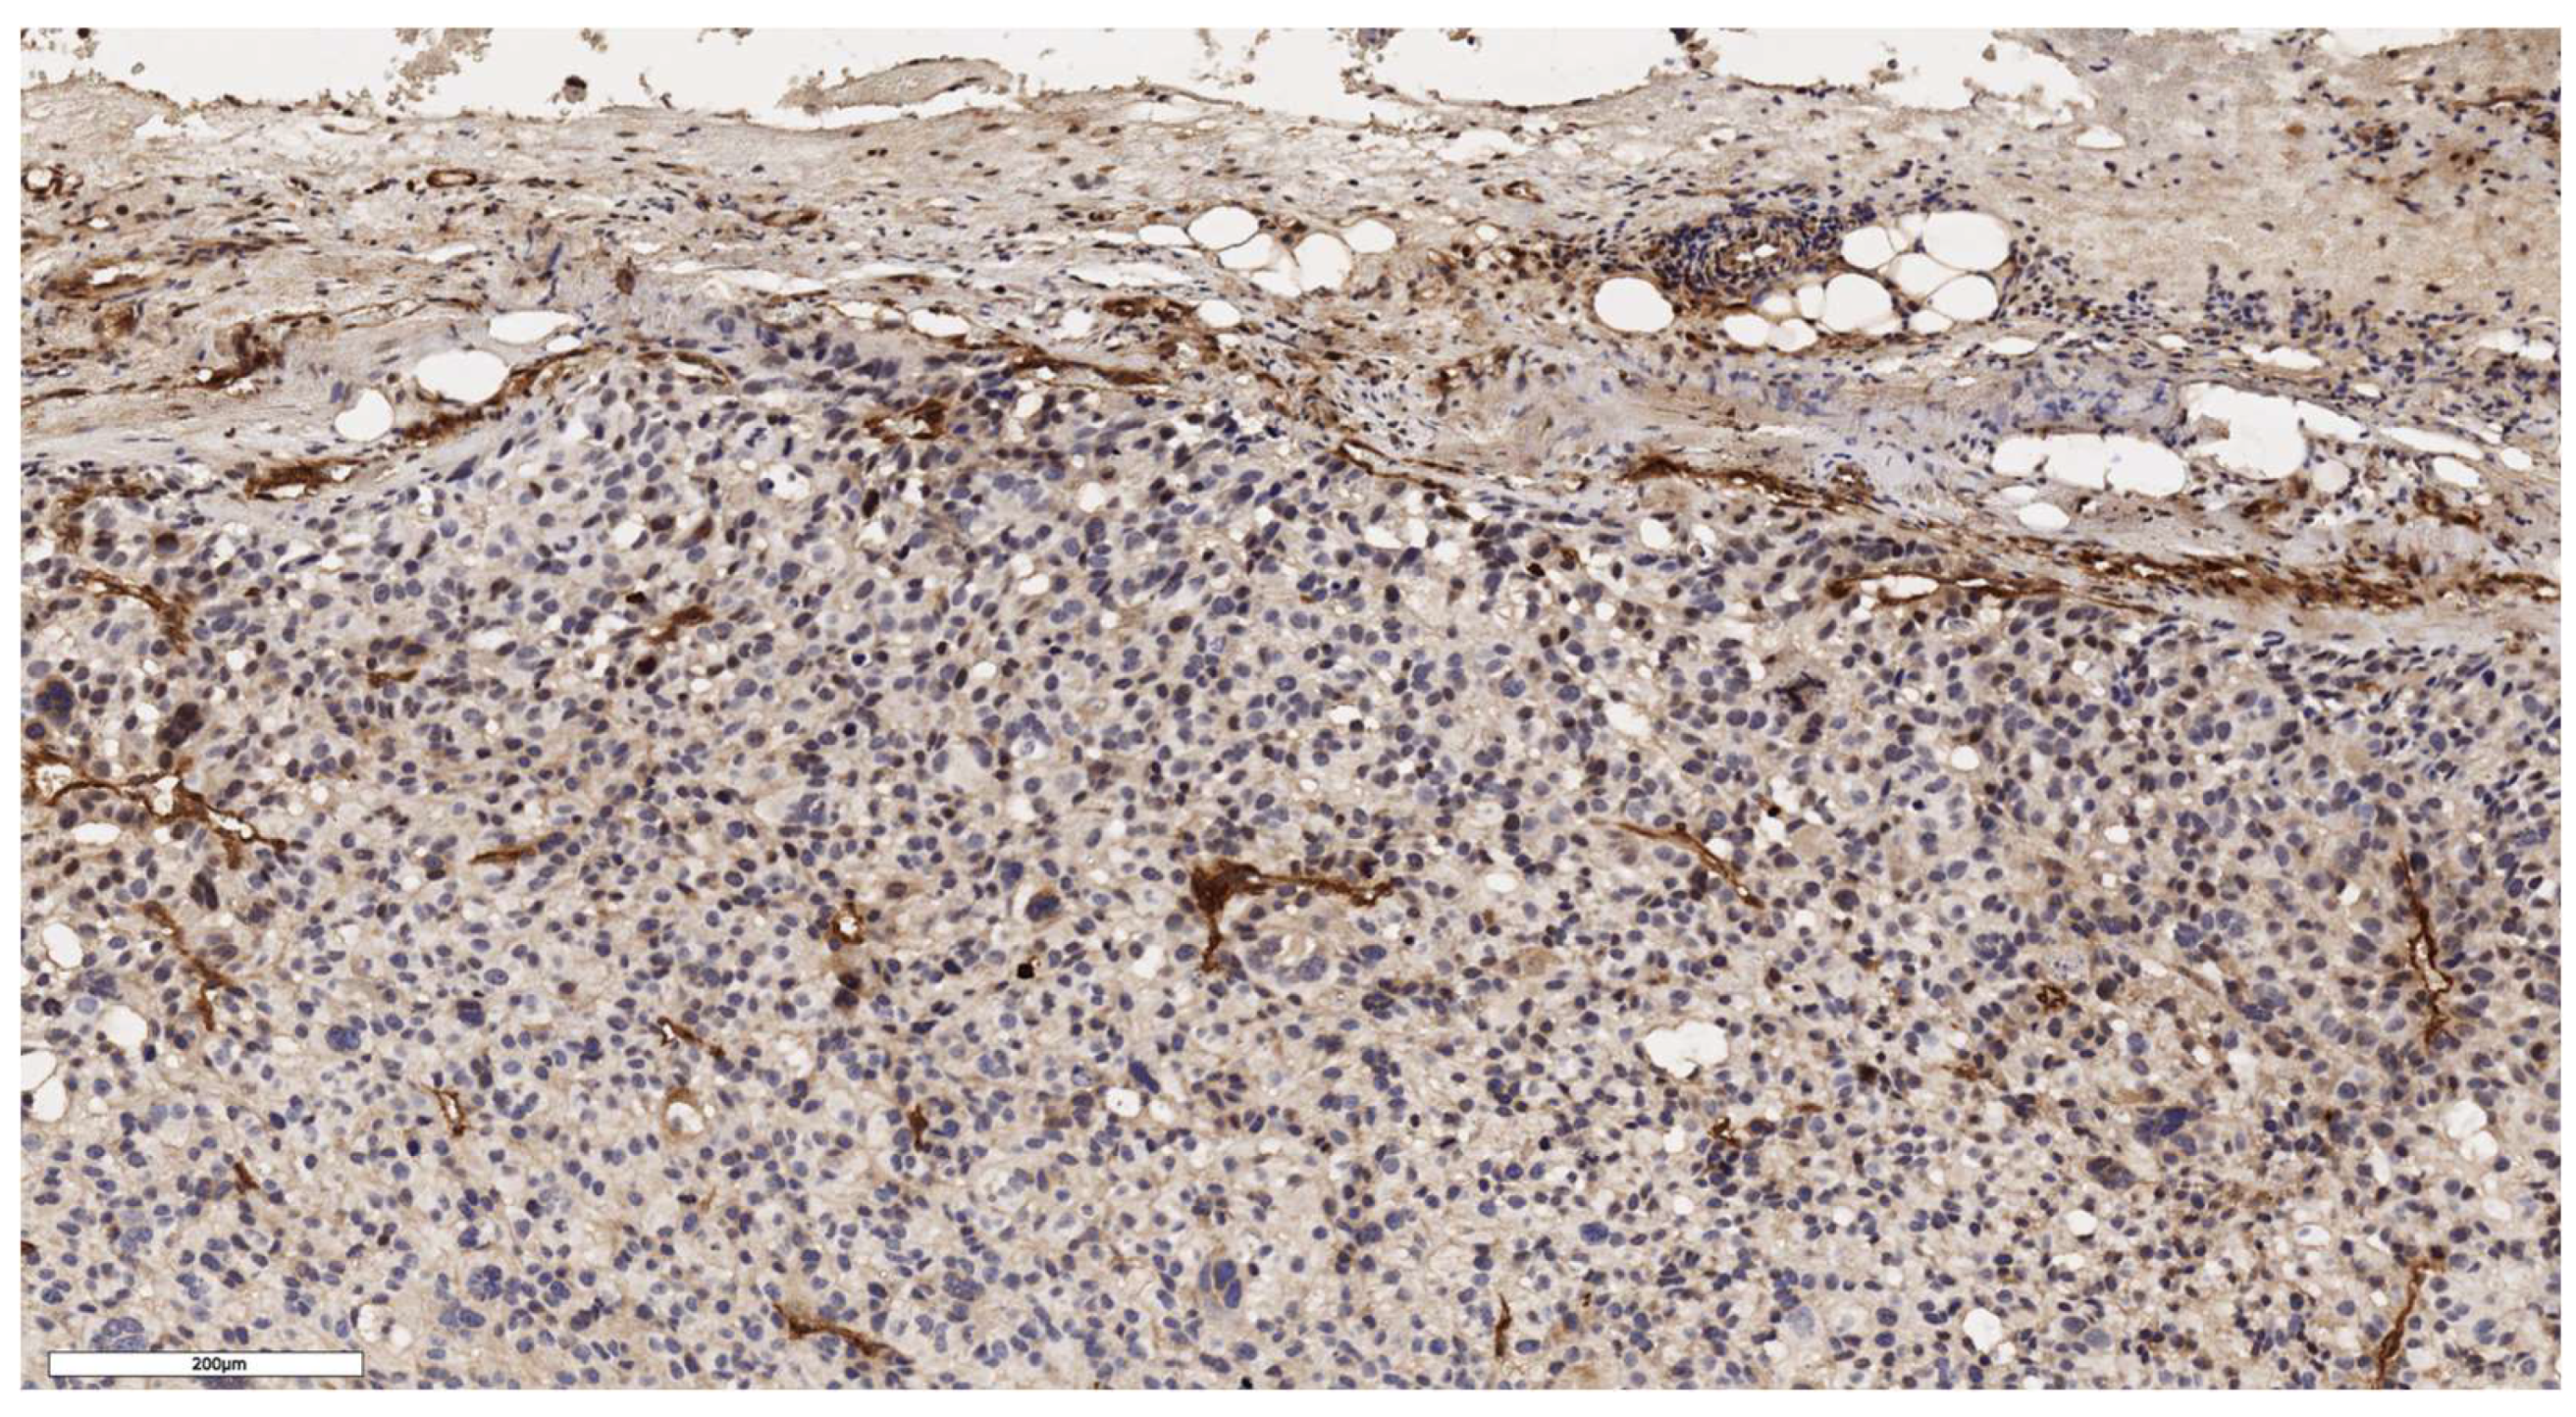

An analysis of the association between CD90 expression and the clinicopathological data of patients was conducted (Table 2). The number of CD90+ cells in the tumor parenchyma was relatively higher in samples of conventional and mixed histological subtypes compared to other histological subtypes of ACC (Figure 2, Figure 3, Figure 4 and Figure 5); however, these differences did not reach statistical significance (p = 0.161). No significant differences in CD90 expression beneath the tumor capsule were found across histological subtypes either.

Figure 2. Conventional subtype of ACC. The parenchyma of the tumor. IHC reaction with CD90 marker, x100.